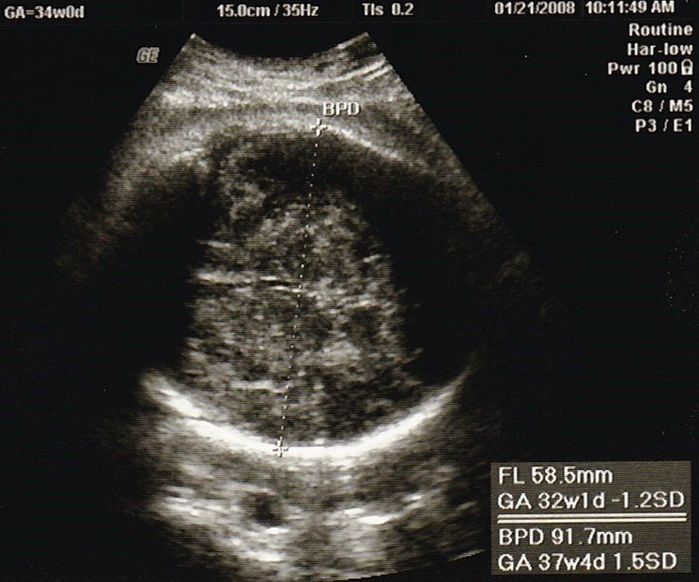

妊娠34週目のエコー写真

最後の血液検査があり、「妊娠37週を超えると正期産に入りますよ」と聞き、「妊婦生活も終わりに近づいているのだな」と感じた検診でした。「今のうちにやりたいことを」と思いましたが、結局、雑誌や本を読むくらいしかできなかったです。美容院に行けなくなるからと、私を含め、髪を切る人が多かった気がします。